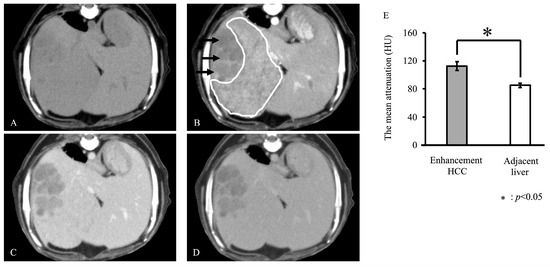

| G2 | enhancement | 13 | IF | Dachshund | - | - |

| G2 | enhancement | 12 | IM | West Highland White Terrier | - | - |

| G2 | enhancement | 7.5 | CM | Toy Poodle | - | - |